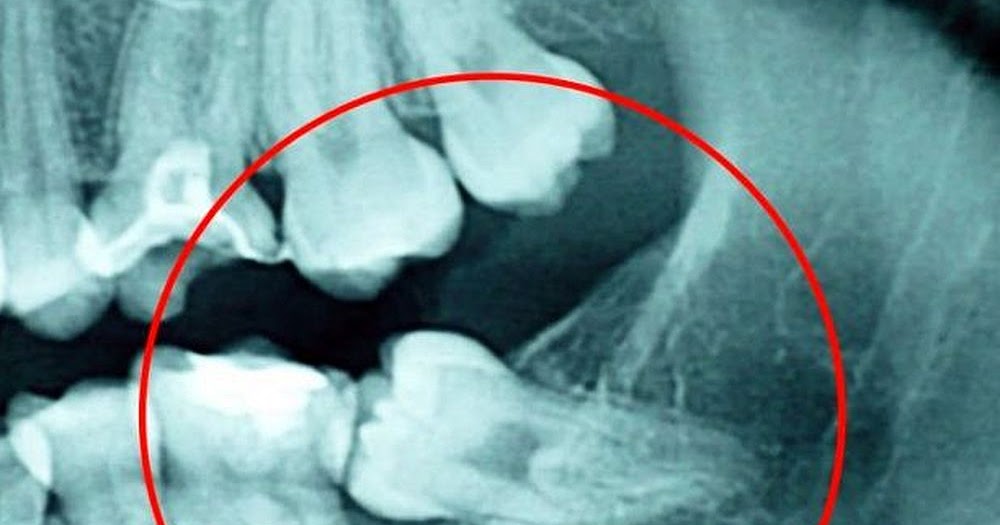

¿Cuándo es necesario extraer las muelas del juicio? | El Metropolitano

WebEl dolor de muela es insoportable, por lo general, producido por una infección. Si bien es cierto que se puede curar, cuando ocurre con frecuencia esto pudiera afectar a otras. WebEl empaste de muela nos sirve para reparar una muela dañada o muela del juicio infectada. Consiste en eliminar la caries de la muela para que no avance de la. Web¿Se puede empastar una muela dos veces? Por supuesto. Es algo relativamente normal y estos son los motivos por los que es necesario hacerlo: Hay que retocarlo. A pesar de. WebUna vez escogido (lo más habitual son los empastes composite) se te aplica anestesia local para dormir la zona. Posteriormente, se utiliza alguna herramienta física,. WebHombre si te han salido correctas las muelas del juicio ,es decir en la direccion correcta no tiened por wue quitartelas... Ya te digo que quitarlas ya qe eso es.